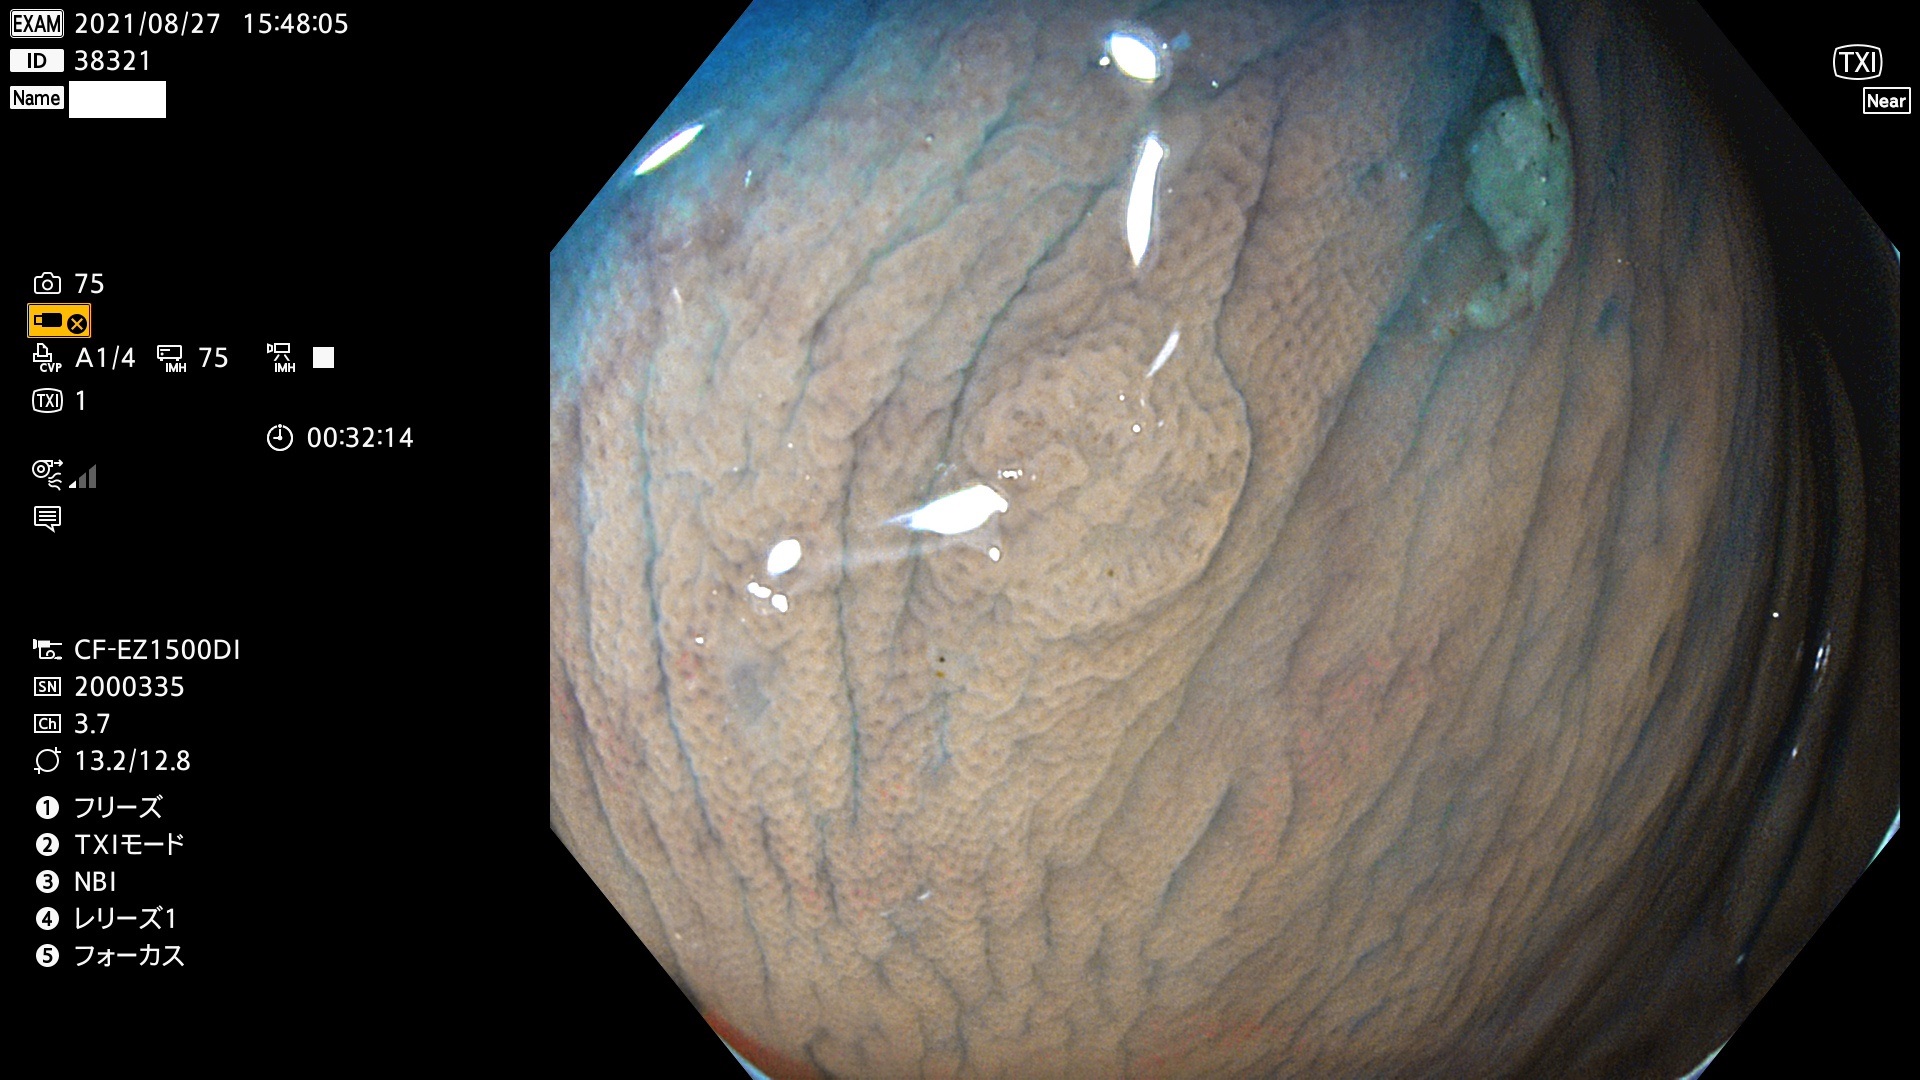

38300 38301 38302 38303 38304 38306 38307 38308 38309 38310 38311 38312 38313 38314 38315 38316 38317 38319 38321 38322 38323 38324 38325 38327 38331 38332 38333 38334 38337 38338 38339 38340 38341 38343 38346 38348 38349 38350 38351 38352 38353 38354 38355 38358 38359 38360 38361 38362 38363 38365 38366(SSAP) 38368 38369 38370 38371(SSAP) 38372 38374 38375 38376 38377 38378 38380 38381 38382 38383 38384 38385 38386 38388 38389 38391(SSAP) 38395 38397 38399

発見困難で危険性の高い平坦型病変(上記100名より抽出)